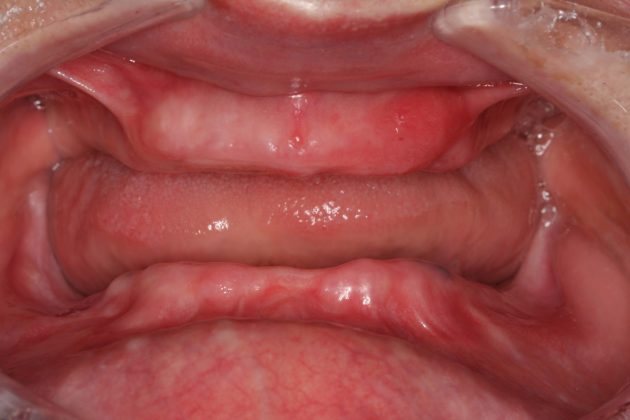

在传统种植牙手术中,医生没有精确的仪器设备判断缺牙位牙槽骨、咬合关系,多借助二维及人工目测的方式,其次,医生也缺乏将正确的诊断和合理的种植方案一丝不差到患者口腔的手段,诸此种种,导致传统种植牙手术只能凭医生的经验来完成,这种以"盲种"的方式,无法对更复杂的缺牙情况进行有效处理,比如半口全口缺牙、咬合关系重建等。

据ICOI院士、ICOI全球大使、麦芽口腔总院长郑苍尚教授介绍,在2000年以后,随着CT精度的提高,锥形束cbct的广泛运用,生产医用模型的3d打印设备和专用材料的成功开发,基于ct影像数据、扫描数据的计算机辅助种植设计软件系统的开发与完善,共同作用下加速了数字化种植牙手术的成熟,其中数字化导板就是数字化种植牙技术中的产物。

郑苍尚教授是国际口腔种植医师学会ICOI全球大使,致力推进先进的数字化种植技术在全球范围内的运用,谈及数字化种牙导板,他浅言,种植牙导板好比司机路上的GPS,它能告诉司机哪条路畅通、哪条路堵塞,能指明种植牙的路径,避开危险的神经与血管,让医生精确控制种牙的位置、角度和深度,除此,还有助于临时修复体的设计制作。

但数字化导板的制备有严格要求,数字化采集入口是一个关键性问题,郑苍尚教授指出,如果数据的获取来源都存在误差,那么导板的功能也将大打折扣。制备数字化导板必须要求精确的数据来源、精确的智能方案设计以及数据云端整合,在数据获取过程避免人工介入,降低人为误差,通过3D打印技术制备的导板才能更符合缺牙市民的实际情况。